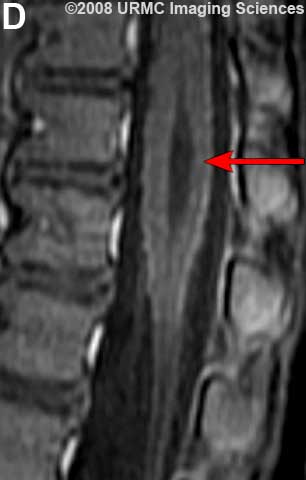

Желудочек терминальный (ventriculus terminalis, PNA, BNA, JNA; син. Краузе желудочек) — расширение в концевом отрезке центрального канала спинного мозга, расположенное в мозговом конусе вблизи от задней его стенки.

Желудочек терминальный

МРТ.  Терминальный желудочек

http://www.radsource.us/clinic/0807